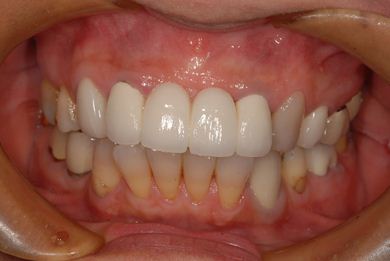

治療後

• 治療後